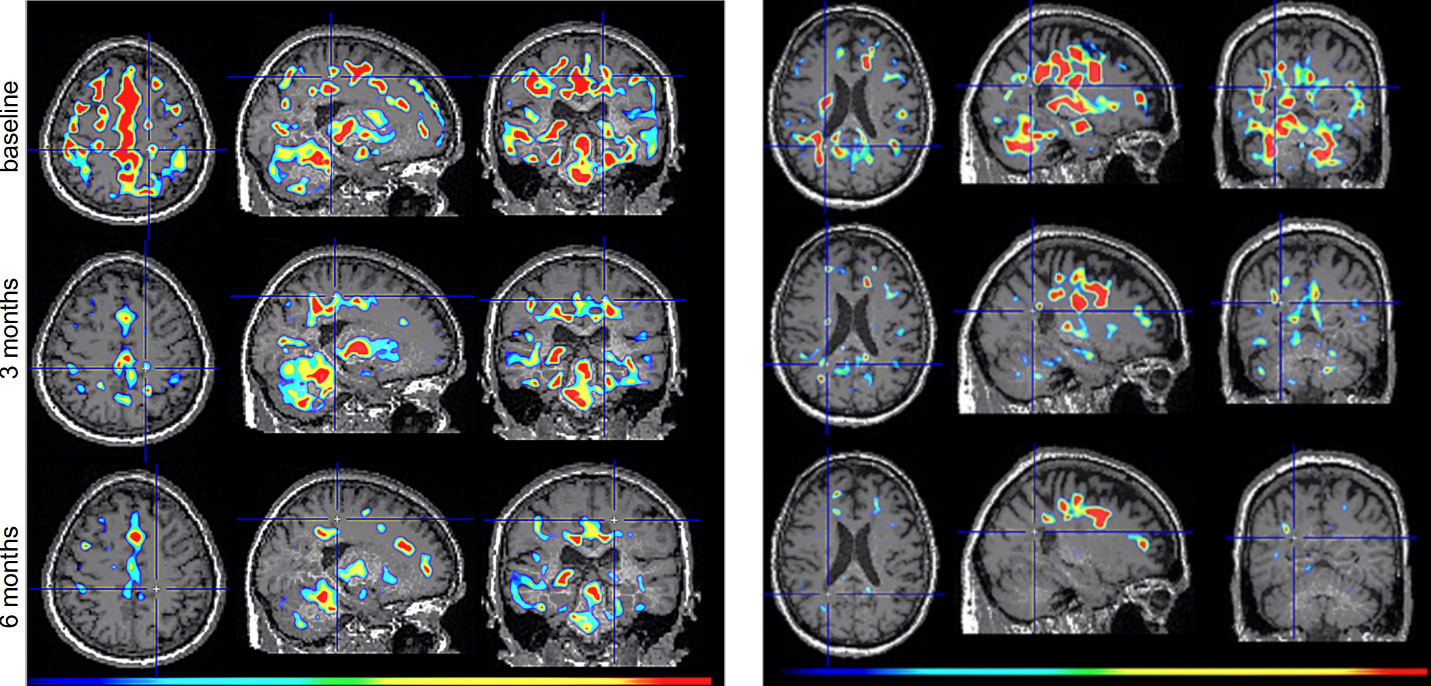

Figure 2. TSPO-PET scans from intranasal foralumab-treated MS patients showing marked reduction in microglial activation over a 6-month treatment period.

Dr. Howard Weiner, Chairman of Tiziana’s Scientific Advisory Board and co-director of the Ann Romney Center for Neurologic Diseases at Brigham and Women’s Hospital, a founding member of Mass General Brigham, stated, “This PET finding is a critical insight: clearing amyloid does not turn off the brain’s inflammatory response. We believe intranasal foralumab directly addresses this residual neuroinflammation by inducing regulatory T cells to migrate to the brain and calm activated microglia — a mechanism we have already shown reduces microglial activation in secondary progressive multiple sclerosis.”

Foralumab, a fully human anti-CD3 monoclonal antibody, is a biological drug candidate that has been shown to stimulate T regulatory cells when dosed intranasally. At present, 14 patients with Non-Active Secondary Progressive Multiple Sclerosis (na-SPMS) have been dosed in an open-label intermediate sized Expanded Access (EA) Program (NCT06802328) with either an improvement or stability of disease seen within 6 months in all patients. In addition, intranasal foralumab is currently being studied in a Phase 2a, randomized, double-blind, placebo-controlled, multicenter, dose-ranging trial in patients with non-active secondary progressive multiple sclerosis (NCT06292923).